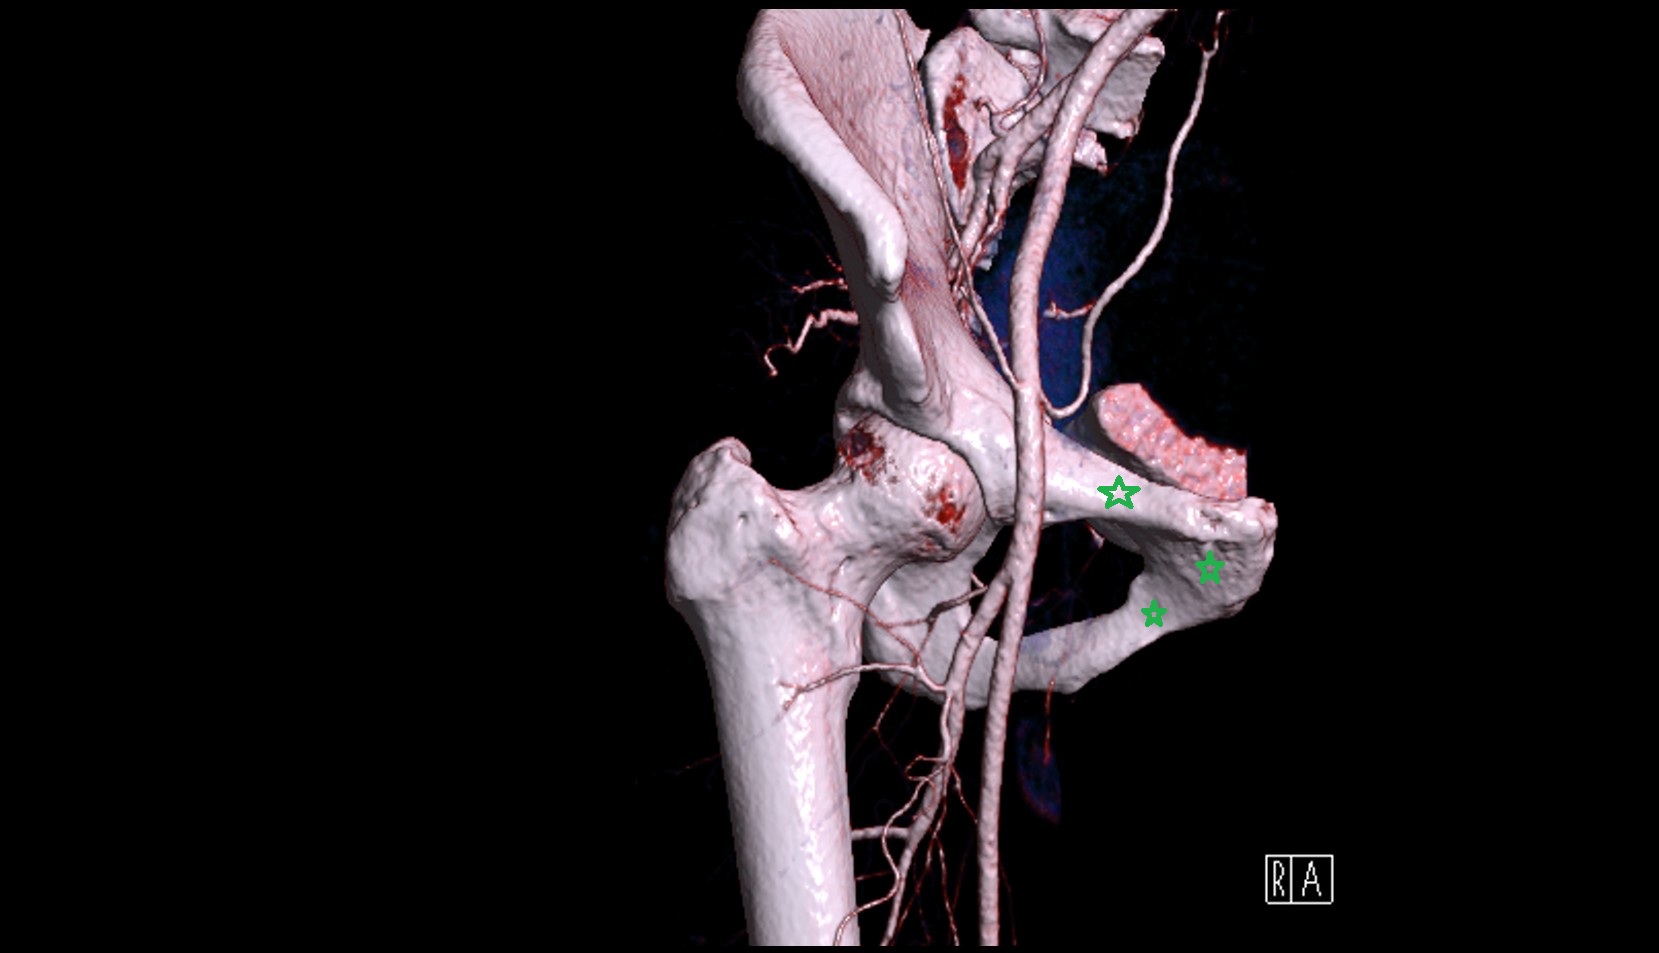

- Inferior gluteal artery

- Lateral circumflex femoral artery

- Deep femoral artery (profunda femoris)

- External iliac artery

- Femoral artery

- Internal iliac artery

- Medial circumflex femoral artery

- Obturator artery

- Superior gluteal artery